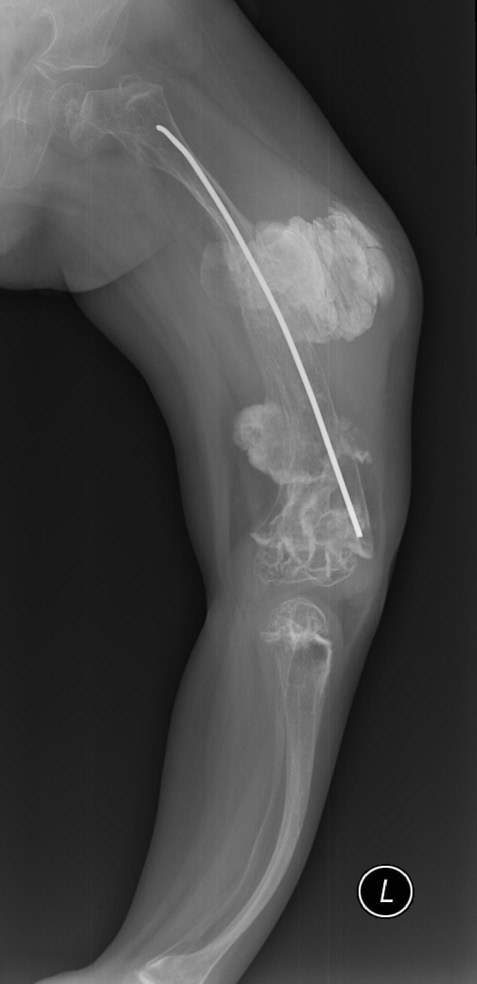

Soft tissues play a key role in the formation of arcuate deformations of long tubular bones. The flexor muscles prevent the bone growth that results in deformity. This is due to the popliteal flexor in the femoral region that leads to anterolateral bending of the bone. This function is performed by the gastrocnemius and fibular muscles in the leg region that cause anteromedial curvature (Fig. 3). Deformed lower limbs lose their biomechanical strength, resulting in increased strain in the deformation apex area that leads to deformation progression and fracture at its height. The purpose of congenital and post-traumatic deformities correction is to reduce the frequency of fractures and ensure the proper growth of the bone to verticalize the child and teach him to walk.

Fig. 3. Deformations of the lower extremities with osteogenesis imperfecta